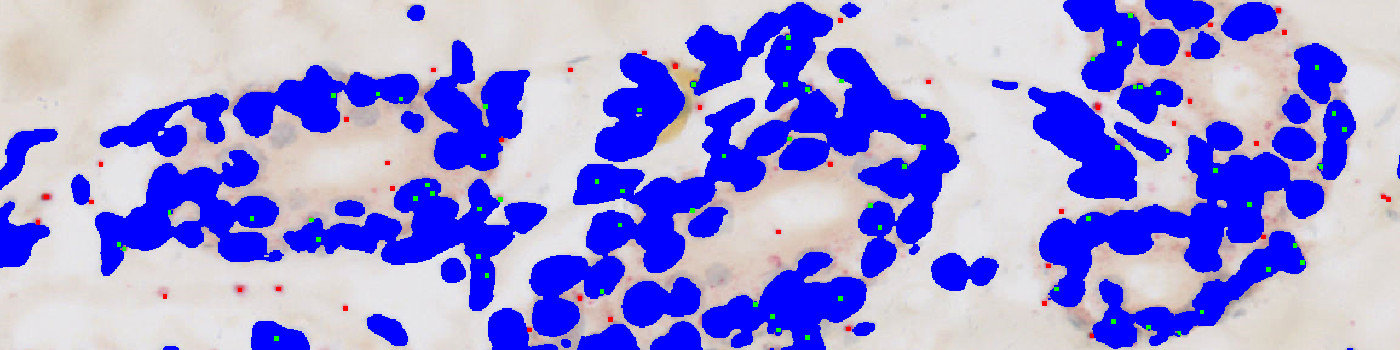

Figure 5

Result of analysis with the APP: “02 Analyze” on the image from FIGURE 4. Nuclei are labeled blue, probes inside the nuclei are labeled green and probes outside the nuclei red.

Figure 6

Zoomed in version of FIGURE 4.

Figure 7

Zoomed in version of FIGURE 5. Nuclei are labeled blue, probes inside the nuclei are labeled green and outside the nuclei red.

The first image processing step involves an automated detection of the dermis and epidermis, i.e. the regions of interest (ROI) (see FIGURE 2). The nuclei and probes are subsequently detected inside these ROIs (see FIGURE 3, 5 and 7). A polynomial blob filter that enhances the probes’ features is used for the identification of the probes, whereas the haematoxylin color-deconvolution band is used for the identification of nuclei. The initial classification of nuclei and probes is managed with a postprocessing protocol to firstly refine the detection of nuclei and probes, and secondly to qualitatively determine if probes are covered by nuclei or not for the final probe quantification. For each tissue type, i.e. dermis and epidermis, probes are counted and categorized as either covered by nuclei or as separate from nuclei.